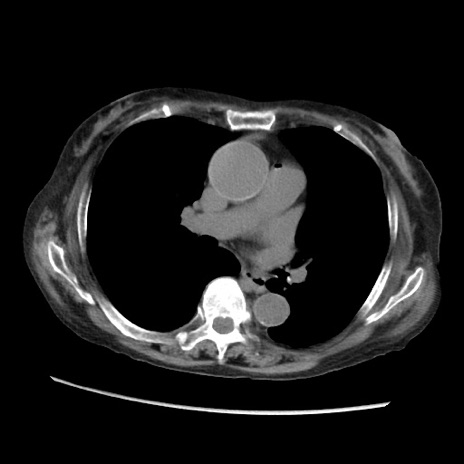

症例31(横断像)

【症例】80歳代 女性

【主訴】腹部膨満感

【現病歴】他院にて肝硬変にてフォロー中。1週間前から便秘、腹部膨満感、臍部腫瘤あり受診となる。

【既往歴】肝硬変

【身体所見】腹部膨隆あり、皮膚変化なし、疼痛なし。

【データ】WBC 4600、CRP 0.25